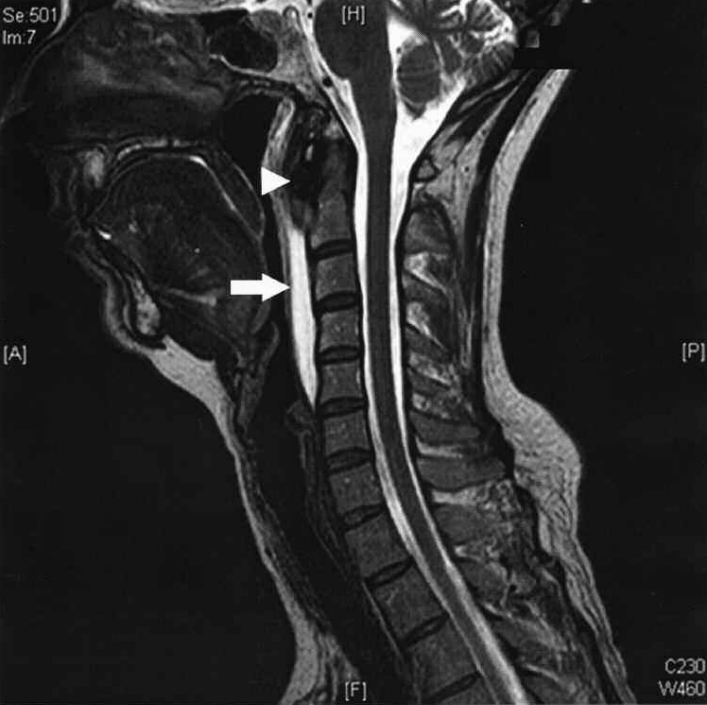

典型病例介绍

36岁女性,急性颈痛、吞咽困难伴颈部僵硬,MRI示C1-2前部颈长肌增厚呈低信号,提示钙化(长箭头)和C1-4椎前积液(无线箭头),经类固醇和止痛药治疗8天后症状消失,复查MRI提示上述表现消失。(PMID: 18765656)

C1-2前侧低信号(无线箭头)和C1-5椎前水肿(长箭头) (PMID: 19567634)